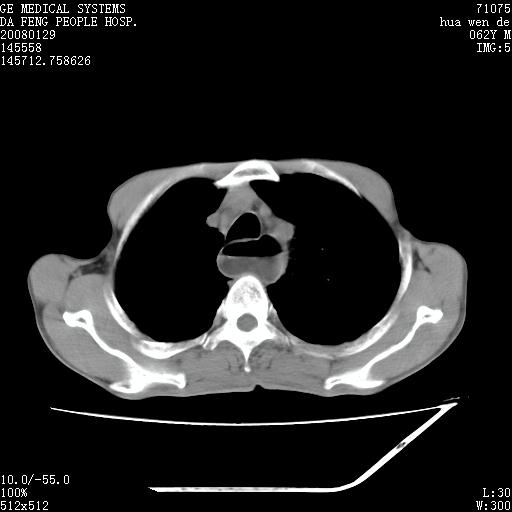

男性,67岁。作肺部检查时发现

右肺脓肿 胸腔胃

考虑1、右肺周围型肺癌可能性大。

2、贲门失迟缓症可能,建议钡餐检查。

考虑:胸腔胃并支气管瘘(并发肺炎,肺脓肿形成)。

理由:1、右上肺内病灶,空洞形成,有液平。

2、肺内多处炎症。

3、前段肺内炎症,支气管引流通畅,与肿块无关系。

1.整个食管扩张,未见明显占位性病变,贲门区亦未见明显占位病变,考虑:贲门失驰缓症;

2.右上肺病变边缘可见毛刺,囊壁厚度不均匀,周围境界较清楚,未见炎性渗出性影,右上肺外带可见片状影,边缘不清,考虑:肺癌伴空洞形成、右上肺炎。

食管全程扩张,壁均匀不厚,喷门失弛缓症

右上肺空洞可见液平,临近肺野磨玻璃密度,考虑1.结核2.脓肿